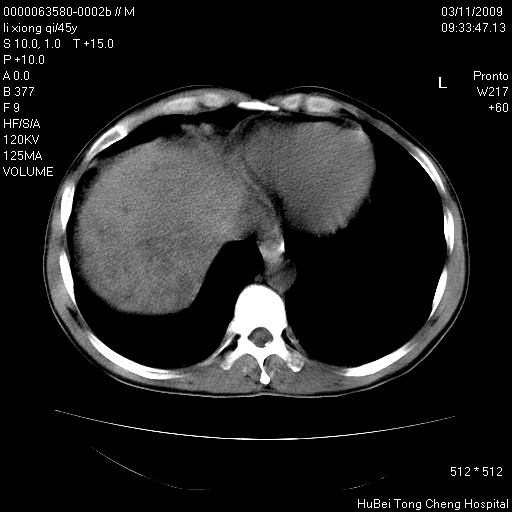

患者 男,45岁。胸痛,咳嗽伴痰中带血1月余。

临床诊断:肺结核?

胸部ct轴位平扫(层厚10mm,螺距1.5,重建间隔10mm),图像如下:

考虑肝癌肺转移